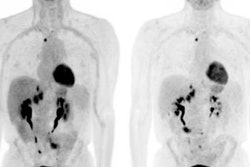

PiB-PET images display Down syndrome-specific templates for carrying capacity (K) and nonspecific Down syndrome (NS) binding. Maps of gray and white matter are displayed for visual reference. K images represent the theoretical limit for the Down syndrome brain to carry beta-amyloid plaques and are in strong agreement with known spatial distribution of plaques in Down syndrome. The highest values are located in the striatum and precuneus. Images courtesy of Zammit et al and SNMMI.Both SUVr and beta-amyloid load increased with age, and both showed similar changes among study participants who already were PiB-positive or who converted to become PiB-positive, Zammit said. However, among PiB-negative cases, beta-amyloid load provided reduced longitudinal variability compared with SUV ratios.